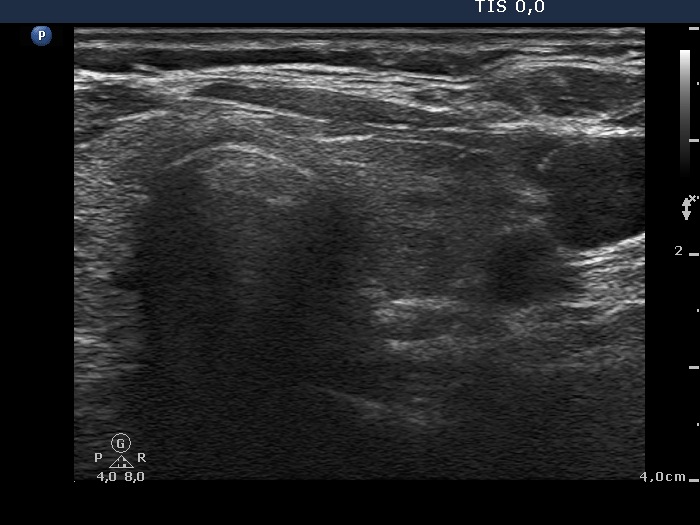

Chronic lymphocytic thyroiditis - Figure 1. Ultrasound patterns according to the degree of hypoechogenicity.

Diffuse hypoechogenicity is the most important sonographic sign of Hashimoto's thyroiditis. The degree of hypoechogenicity varies greatly, and correlates relatively well with aTPO level. We have to notice the hypoechogenicity in a euthyroid patient in order to consider the possibility of the underlying autoimmune thyroid disease and therefore to give the chance to recognize hypothyroidism later.

A hypoechogenic thyroid is presented with fibrotic changes.